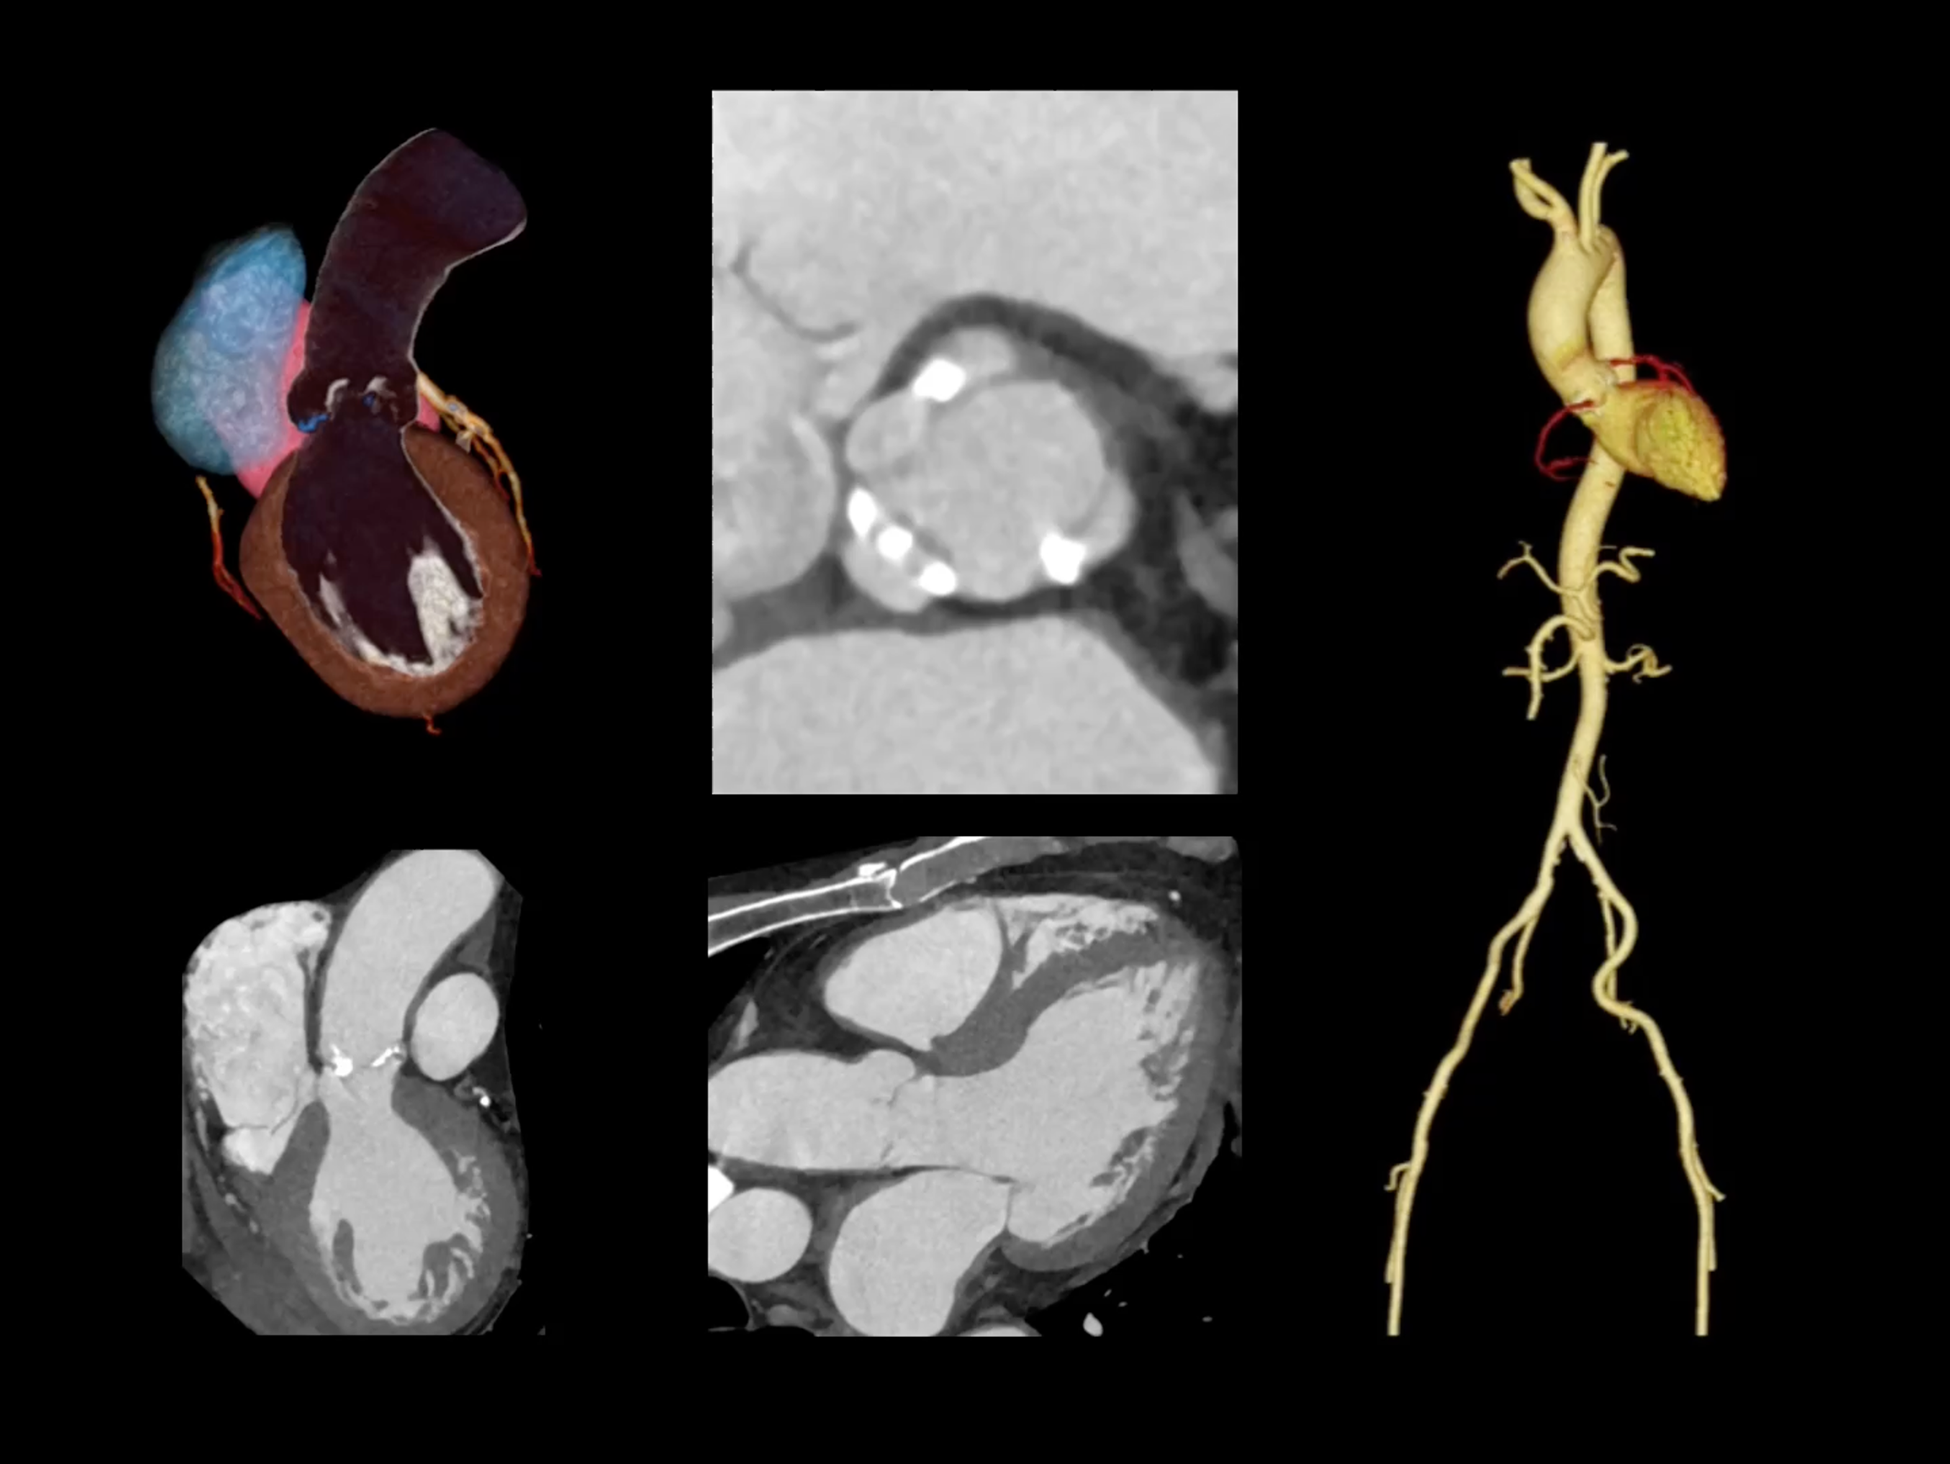

uCT SiriuX® 依托16cm超宽探测器与双源能谱技术,实现真正意义上的全身高清能谱成像。单次扫描同步获取灌注、能谱等多维定量参数,精准解析组织特性与病灶成分,为临床决策提供更深层次的诊断依据。

能谱成像可揭示丰富的物质与能量信息,其临床价值的充分释放有赖于完善高效的后处理分析平台。uCT SiriuX® 提供全面能谱高级分析工具,覆盖心血管、肿瘤、神经、骨科等多类临床场景。平台支持动脉增强分数分析(AEF)、细胞外容积分析(ECV)、肿瘤同源性分析、肺栓塞分析、骨髓水肿分析等多项评估,并提供多达10种基物质对成像,为精准诊断与科研探索提供坚实支撑。